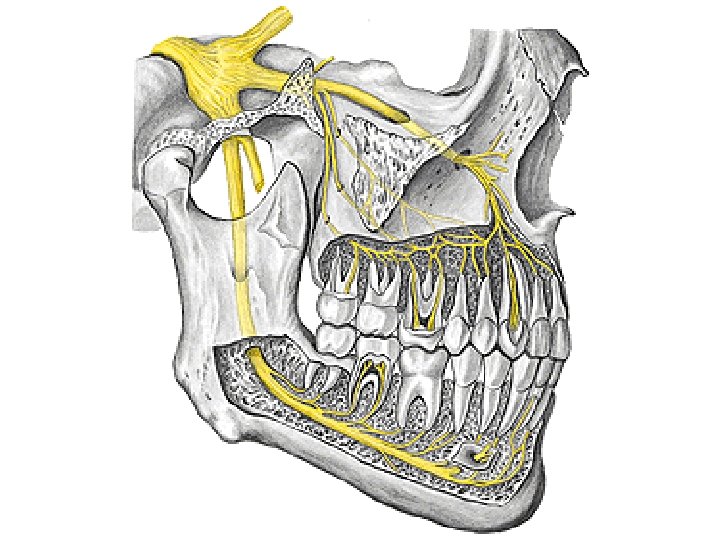

N. lingualis N. glossopharyngeus (CN IX) N. hypoglossus (CN XII) A. lingualis